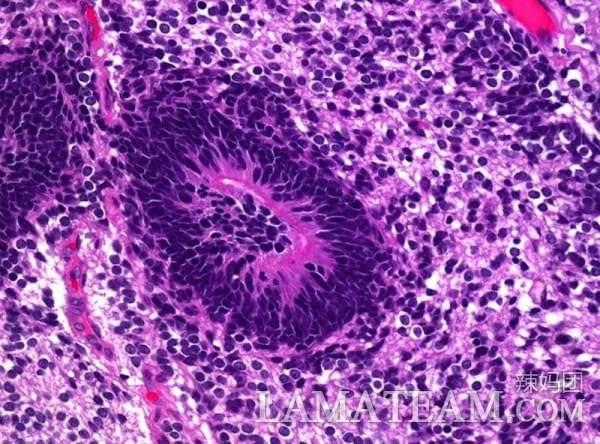

最後醫生做了活組織切片,結果表明路易斯患了未成熟卵巢畸胎瘤。

這種未成熟卵巢畸胎瘤高發於20出頭的年輕女性。